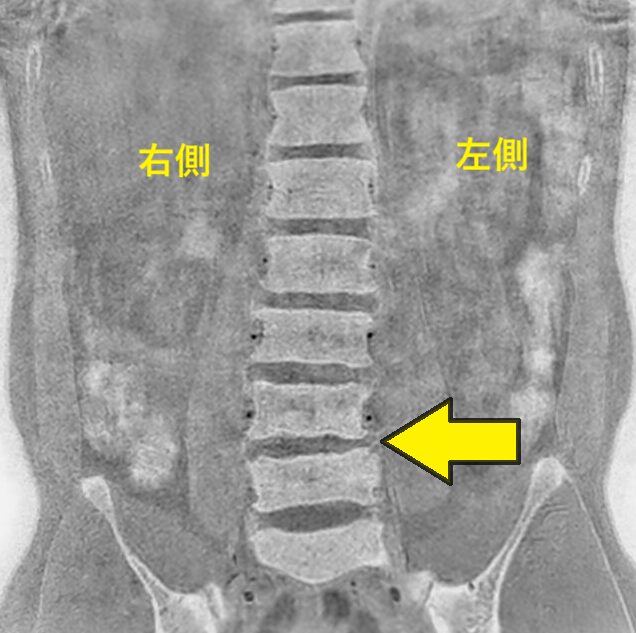

ご自身で持参されたMRI画像

(ウエストラインの左右差あり)

- ウエストラインは左が狭い:黄色矢印